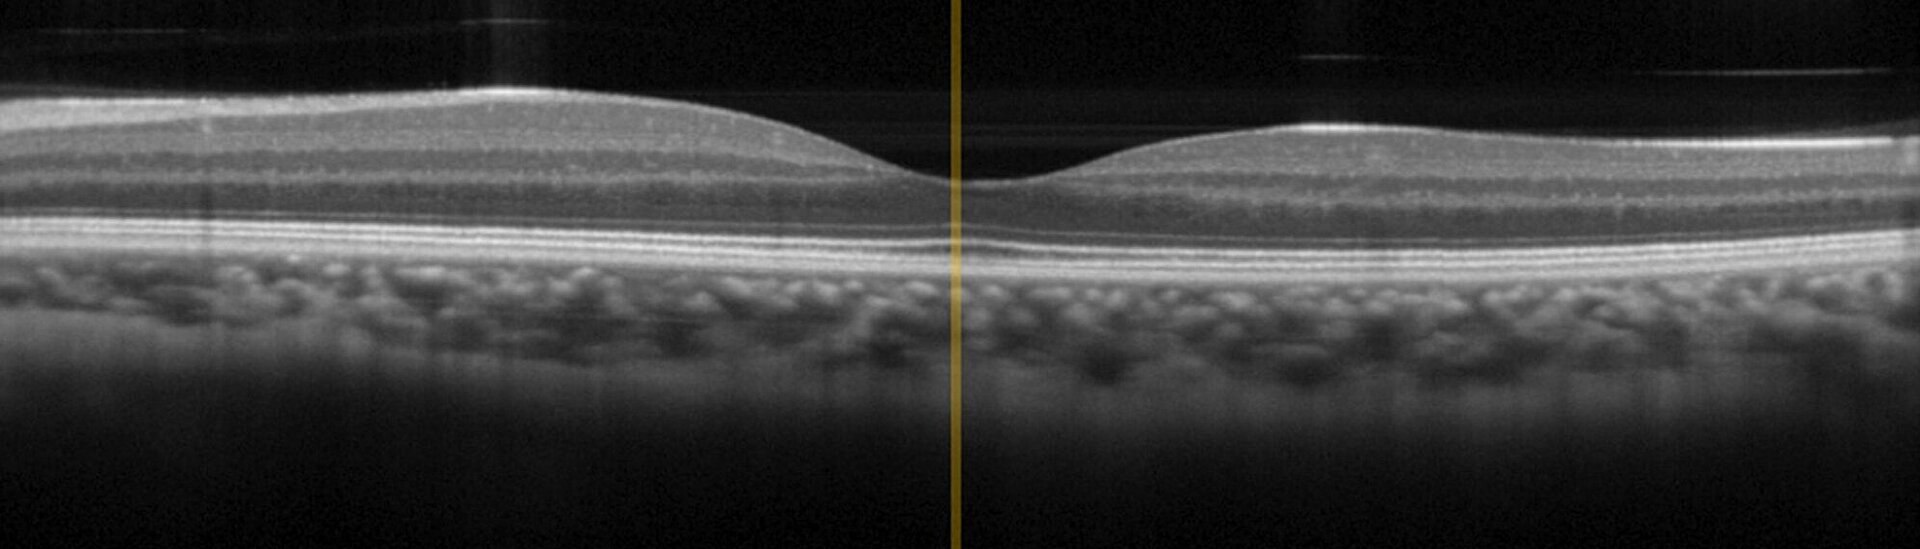

Scanning Stages for Fast and Reliable Image Acquisition in OCT Devices for Ophthalmology and Dermatology

OCT is an interferometric imaging technique based on broadband infrared light in the wavelength range between 0.8 µm and 1.4 µm for optimal tissue penetration. OCT has already achieved "Gold Standard" in ophthalmology but recently also finds growing application in dermatology, for example to diagnose skin cancer. In comparison to conventional invasive diagnostic measures, OCT delivers results faster and reduces side-effects and stress on patients.

The OCT technology uses broadband IR light (in the wavelength region between 800 - 1400 nm due to best penetration in tissue) with short coherence lenght in a Michelson interferometer setup. The signal is a result of the interference from probe- and reference-beam, based on reflections at refractive index boundaries within biological tissue.